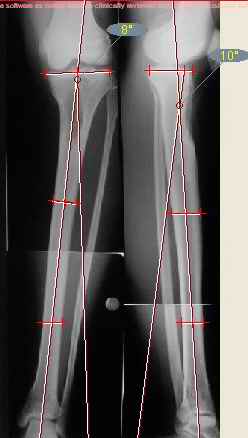

Продолжение обсуждения, начатого в октябре прошлого года (см. здесь) Наконец-то оперировали эту пациентку. Биопсию сделали - опухолевого ничего нет. Пока все участвовавшие в обследовании смежные специалисты и ортопеды сошлись, что это молокальная монооссальная фиброзная дисплазия. 20 марта наложили аппарат, сделали чрескожную остеотомию. К 3 апреля все докрутили. Сегодня заштифтовали. Начальные и итоговые снимки в приложении. Рекурвацию можно было еще немного больше устранить, и чуть кзади сместить диафиз. Но вроде и так ничего выглядит, по сравнению с тем, что было. Комментарии приветствуются.

ничего не понимаю в детской и ортопедии, но в боковой проекции нет рекурвации,

а даже немного гиперкоррекция, что по-моему есть хорошо. Кортикалы по задней стенке совпадают, диафиз на одну неправду кзади.

Александр, по моему великолепно. Поздравлять будем, когда продемонстрируете консолидацию,функцию и внешний вид.

Вопрос: почему дистально только один винт? Предполагаете ли динамизацию?